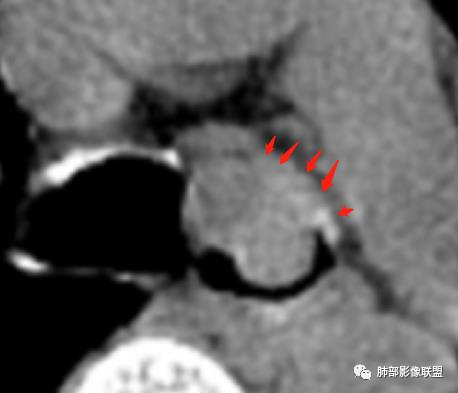

2、局部软骨不连续,壁外有增厚,提示局部软骨破坏,壁外有病灶

二、影像表现:肿瘤好发于气管后壁软骨和膜部连接处,这与该部位黏液腺较多有关,沿气管粘膜下延伸,呈腔内息肉样或宽基底的软组织密度肿块,沿管壁梭形生长,长径大于短径(具有粘膜下浸润生长的特性所致),管壁弥漫或全周增厚,伴管腔不同程度狭窄,肿瘤可同时侵犯腔内外,形成腔内外软组织肿块。平扫密度均匀,呈软组织密度,瘤内坏死钙化少见。增强后病灶呈不同程度均匀或不均匀轻中度强化,肺内转移常见。

2.类癌:典型类癌绝大多数为中央型。对于成年人,更常见于女性。累及主、叶、段支气管,远端朝外侵犯,一般不是周围环形壁增厚;腔内外生长-冰山征;血供丰富、显著强化,可有钙化。